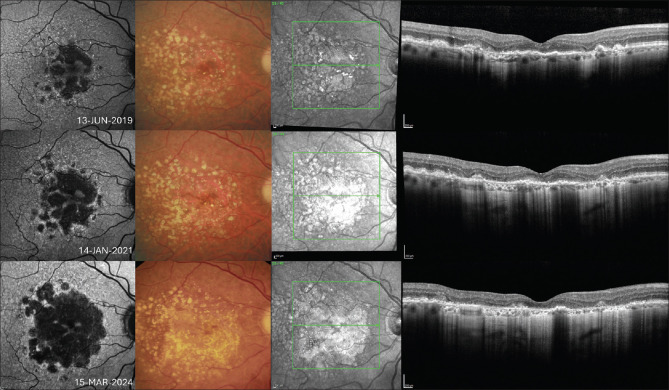

As we move toward an era in which there will be treatment options for geographic atrophy (GA) secondary to age-related macular degeneration, the need to accurately understand and interpret multimodal imaging (MMI) for the condition is paramount. This review discusses the evolution of MMI in GA and how it has led to a greater understanding of different phenotypes and risk factors for progression. These advancements have allowed novel imaging biomarkers to be used as end points in large interventional studies exploring new therapies for GA treatment. Due to differences in drug approval timing, ophthalmologists in some jurisdictions are already treating patients with complement inhibiting intravitreal therapies and using MMI to guide management. Cementing knowledge of how GA appears on MMI and evolves over time will be vital for best practice as these interventions become more widely available.